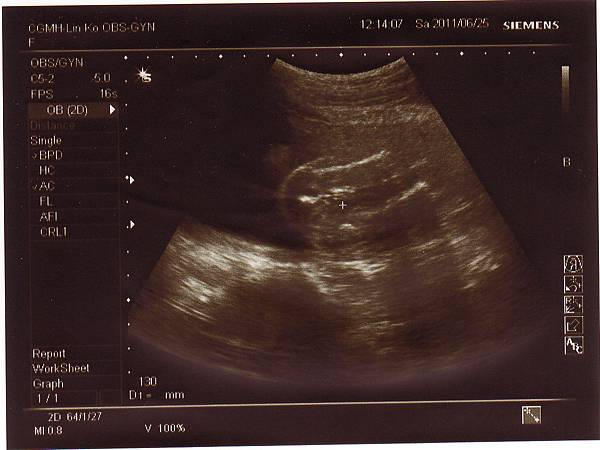

2011.06.25 當天先去超音波室做了仔細的超音波檢查,

檢查心臟.是否兔唇.手腳.肺動脈....等等,

一切都非常正常,也確定是個兔女郎!

只是後來到診間時,醫生聽寶寶心跳有幾秒是比較慢的,

又加上那天我的血壓超低(88/41),

因此為了安全起見,醫生要我兩個星期後再來一趟~